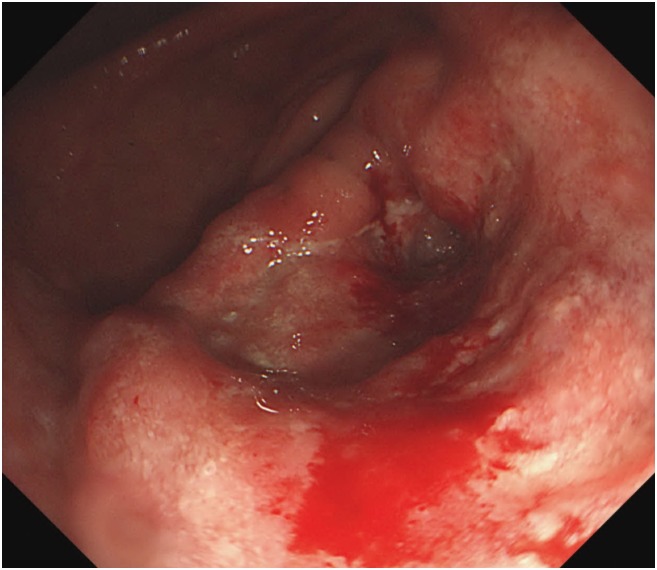

A 57-year-old man was informed regarding a possible diagnosis of gastric cancer at a local clinic on November 15, 2016, based on the results of endoscopic examination previously performed following his complaints of weight loss, abdominal pain, and indigestion. On the same day, the patient visited the department of gastroenterology at a university hospital for endoscopy including biopsy. The tests revealed advanced gastric cancer in the distal antrum (Fig. 1). Abdominal computed tomography (CT) scans subsequently confirmed the presence of cancer and metastasis. The results showed invasion of the entire wall of the antrum with regional lymph node metastasis (Fig. 2). He was diagnosed with stage IIIB gastric cancer (T4N2M0). On December 6, 2016, the patient underwent subtotal gastrectomy with Billroth I anastomosis and cholecystectomy, and was started on chemotherapy. Despite the treatment, he died of gastric cancer on January 9, 2018. Apart from having received treatment for chronic hepatitis B, the patient had never been diagnosed with any disease of the GI tract prior to the gastric cancer diagnosis. During the endoscopy performed on November 15, 2016, he was not tested for H. pylori infection; in addition, he never underwent any tests for H. pylori infection. We were thus unable to determine the presence of H. pylori infection. He had a 1–10 pack-years history of smoking, did not drink, and had no particular relevant family medical history. At the time of his job history survey, the patient was working as a day laborer; his official job history could not therefore be established. We accordingly reviewed his employment insurance records, the National Tax Service (NTS) reports, and his own statements. Based on the combined information, we summarized that the patient had worked as an oxygen cutter at shipbreaking workplaces from 1978 to the 1990s (for approximately 17 years). Furthermore, during the 1990s and 2010s (until 2016), he worked for 7 years at building demolition workplaces as a member of the boiler dismantling crew, and also spent another 14 years in dismantling factories and various thermal power generation plants. Altogether, the patient had presumably worked for about 40 years since 1978 as an oxygen cutter at workplaces that dismantle ships, buildings, boilers, and thermal power plants.

Fig. 2

Patient A: abdominal computed tomography images. Abnormal wall thickening and enhancement in the gastric antrum with regional lymph node enlargement.